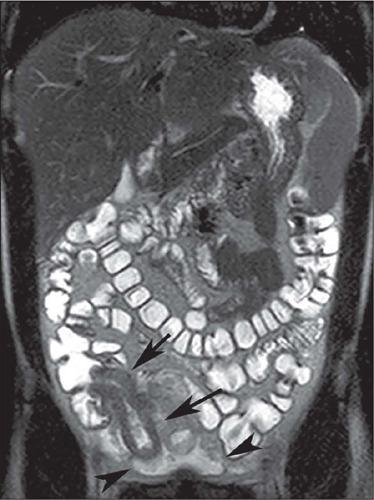

Crohn's disease is an inflammatory bowel disease that can affect any segment of the gastrointestinal tract. It has a variable clinical course, with alternating periods of disease activity and remission. Because the incidence and prevalence of Crohn's disease have been increasing, evaluation by imaging methods has become more important. The most widely used methods are computed tomography enterography, magnetic resonance enterography (as an elective examination), and contrast-enhanced computed tomography (in the context of emergency). Computed tomography enterography and magnetic resonance enterography are useful for diagnosis, follow-up, evaluation of complications, and prognosis. Both can be used in order to evaluate the small bowel loops and the associated mesenteric findings, as well as to evaluate other abdominal organs. They both also can detect signs of disease activity, fibrosis, penetrating disease, and complications. The interpretation of such changes is essential to the multidisciplinary approach, as is the standardization of the nomenclature employed in the reports. In this paper, we review and illustrate the imaging findings of Crohn's disease, using the standardized nomenclature proposed in the multidisciplinary consensus statement issued by the Society of Abdominal Radiology, the Society of Pediatric Radiology, and the American Gastroenterology Association, with recommendations for descriptions, interpretations, and impressions related to those findings.

克罗恩病是一种炎症性肠病,可累及胃肠道的任何节段。其临床病程多变,疾病活动期和缓解期交替出现。由于克罗恩病的发病率和患病率一直在上升,通过影像学方法进行评估变得更加重要。最常用的方法是计算机断层扫描小肠造影、磁共振小肠造影(作为选择性检查)和增强计算机断层扫描(在急诊情况下)。计算机断层扫描小肠造影和磁共振小肠造影对诊断、随访、并发症评估及预后判断均有帮助。两者均可用于评估小肠肠袢及相关肠系膜表现,以及评估其他腹部器官。它们还都能检测疾病活动、纤维化、穿透性病变及并发症的征象。对这些改变的解读对于多学科诊疗方法至关重要,报告中使用的命名标准化也同样重要。在本文中,我们使用腹部放射学会、儿科放射学会和美国胃肠病学会发布的多学科共识声明中提出的标准化命名,回顾并阐述克罗恩病的影像学表现,并对与这些表现相关的描述、解读及印象给出建议。